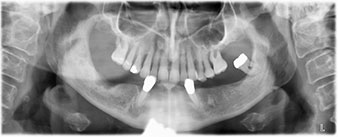

Para la planificación y la minimización del riesgo, se realizó una tomografía volumétrica tridimensional (TVD, Planmeca) que mostró que la calidad y la cantidad del tejido óseo era suficiente para la intervención quirúrgica y el tratamiento inmediato con el método Fast & Fixed. Siguiendo el protocolo de este método, se insertaron los implantes en la región de las piezas 35, 32, 42 y 45. Debido a la inclinación de hasta 45 grados de los implantes distales, el perfil de emergencia se desplazó hacia posterior y se generó un mayor polígono de soporte (fig. 3).